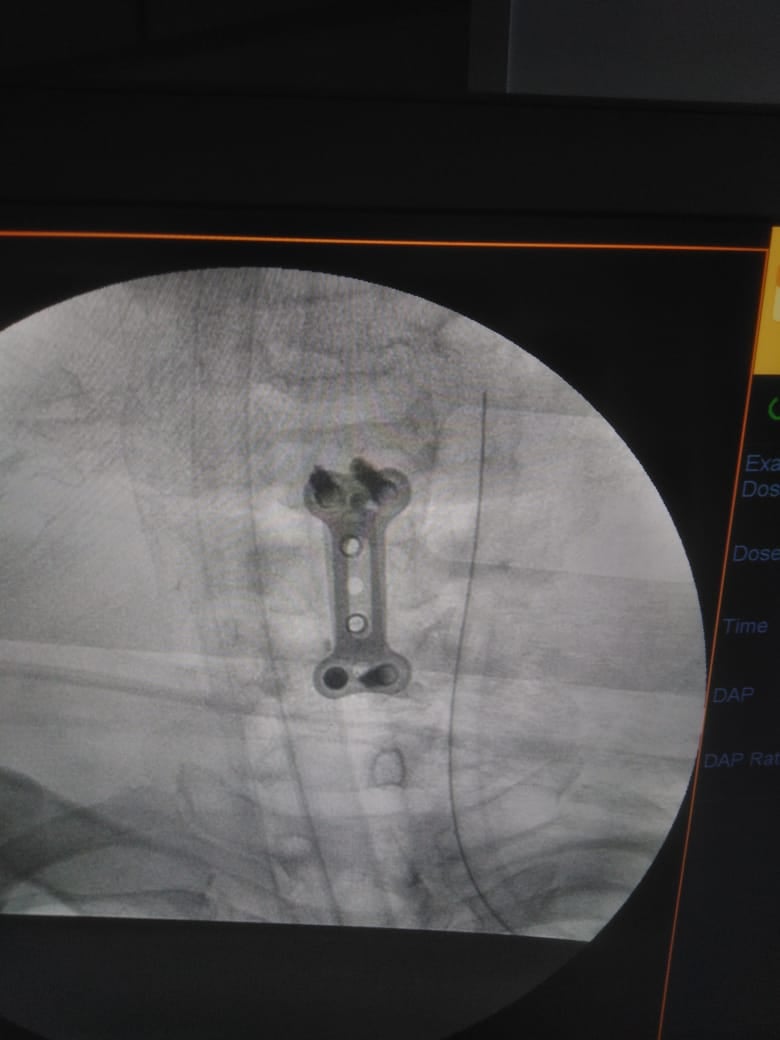

وشهدت الجراحة استئصال الفقرة الخامسة «المفتتة» ووضع دعامة عنقية وتثبيتها بواسطة شريحة ومسامير وتوسيع القناة العصبية.

وأوضح أخصائي جراحة المخ والأعصاب، أن تلك العملية تعد من العمليات الرائدة في مجال جراحات العمود الفقري في الإسكندرية، مشيرًا إلى استقرار حالة المريض عقب إجراء الجراحة، ودخوله غرفة العناية المركزة بالمستشفى تحت المتابعة المستمرة من أطباء المستشفى.

وشارك الدكتور أحمد الرحماني، في إجراء الجراحة بمعاونة هدى فتوح، ومينا عاطف، فني الأشعة.